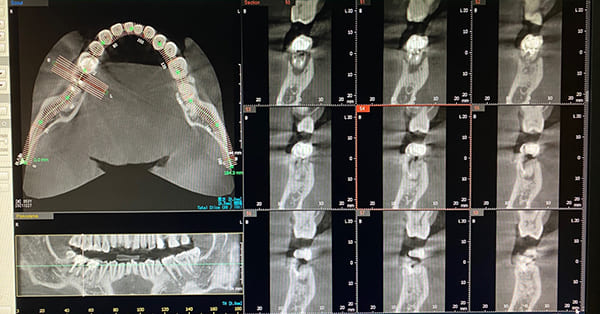

- CT撮影により

安全で正確な抜歯が可能

精密なCT画像で診断

下顎の骨内には神経と血管が通る下顎管があり、親知らずがこれに近い場合や接している場合、抜歯後に痺れなどの症状が出ることがあります。